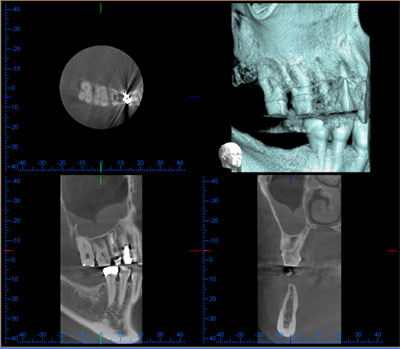

歯科用コーンビームCT

- 歯科用コーンビームCTとは?

- 歯科(口腔領域)専用に開発されたコンピュータ断層撮影装置(Computed Tomography)で

コーンビーム方式を用いるためCBCT(コーンビームCT)と呼びます。

撮影したデータをコンピュータで処理して3次元で表示します。

当院はモリタ社製歯科用コーンビームCT ベラビューエポックス3Dを使用しています。

- 歯科用レントゲンとどう違うの?

- 従来の歯科用レントゲンは、2次元(平面)で歯や顎の骨を観察していましたが、

CBCTでは、3次元(立体的)で診ることができます。

複雑な歯根や顎の骨の形を精確に診断できるので、歯の根の治療、抜歯、歯周外科、歯科インプラント治療など

ほとんどの歯科治療の際に非常に有効です。

- 一般的なCT(ヘリカルCT)と比較すると?

ヘリカルCTとは違い撮影方式など歯科用に設計されているので利点・欠点があります。利点

被曝線量が少なく撮影時間が短い。高解像度(ヘリカルCTの8倍程度)

金属による画像の乱れ(金属アーチファクト)が少ない。欠点

軟組織(歯、骨以外)のコントラストが出にくい。

撮影範囲が限られる(口腔領域のみ)。*歯科用CTは保険適応外ですので費用は自己負担となります。